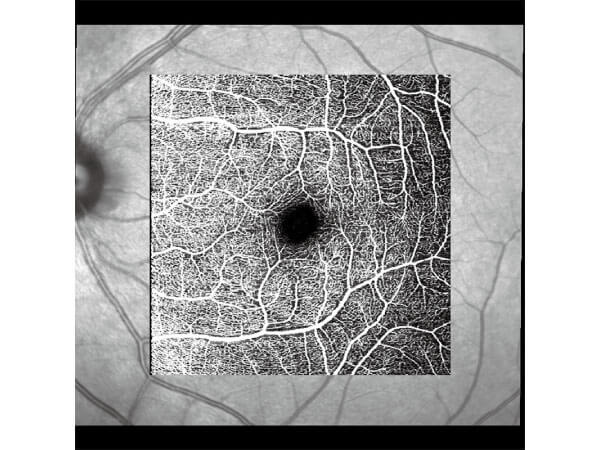

醫療設施:免打顯影劑 血管斷層掃瞄儀

眼底視網膜病變免打顯影劑避免過敏等嚴重副作用